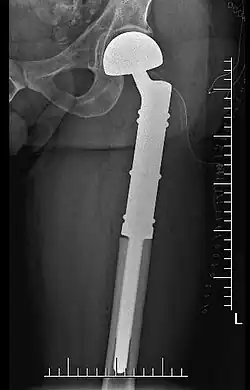

Endoprotezoplastyka, alloplastyka, endoplastyka – zabieg chirurgiczny polegający na wycięciu zmienionego chorobowo segmentu organizmu (np. stawu) i wszczepieniu elementu sztucznego, przejmującego funkcję uszkodzonej struktury.

Zabieg endoprotezoplastyki jest stosowany w leczeniu zmian zwyrodnieniowych oraz w wielu urazach (złamania szyjki kości udowej, złamania w okolicy krętarza). Endoprotezoplastyka jest ponadto elementem oszczędzającego kończynę leczenia nowotworów kości – mięsaków (mięsak Ewinga, kostniakomięsak, chrzęstniakomięsak). Polega ono na zastąpieniu naturalnego stawu sztucznym stawem – endoprotezą. Zabieg endoprotezoplastyki przeprowadza się w znieczuleniu zewnątrzoponowym (bez narkozy) lub w pełnym znieczuleniu (w przypadku rozleglejszych zabiegów, np. onkologicznych). Zabieg, poprzez wyeliminowanie bólu, przywraca utracone czynności tego stawu i umożliwia wykonywanie podstawowych ruchów (chodzenie, podnoszenie ciężarów). Warunkiem osiągnięcia tego celu jest wyeliminowanie towarzyszącego urazom i zmianom zwyrodnieniowym bólu. Podstawą w zachowaniu pacjenta po zabiegu endoprotezy jest oszczędzanie i zapobieganie przeciążenia stawu operowanego. Po wszczepieniu endoprotezy niezbędna jest rehabilitacja, w celu uzyskania możliwie pełnej sprawności osoby operowanej.